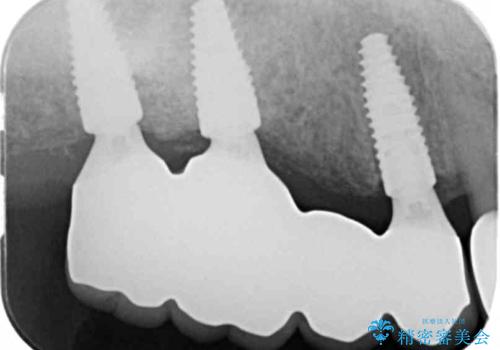

- 「歯がぐらぐらして噛めない、歯を抜いて欲しい、またしっかりと噛めるようになりたい。」、と歯周病治療を希望され来院されました。

歯の根本まで骨吸収が進み、ぐらぐらになってしまった歯を抜去し骨の造成を行ったのちインプラント治療を計画します。

重度に吸収してしまった歯槽骨をしっかりと造成を行ったのちにインプラント治療を行ったので、安定した歯周環境にすることができました。